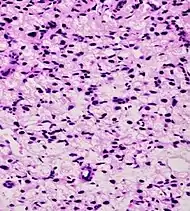

Intraductal carcinoma of the prostate with very patchy basal cells identified by immunohistochemistry. At least some of the glands lacking basal cell immunoreactivity represent intraductal rather than invasive carcinoma (a haematoxylin and eosin, b CK 5/6)[19]